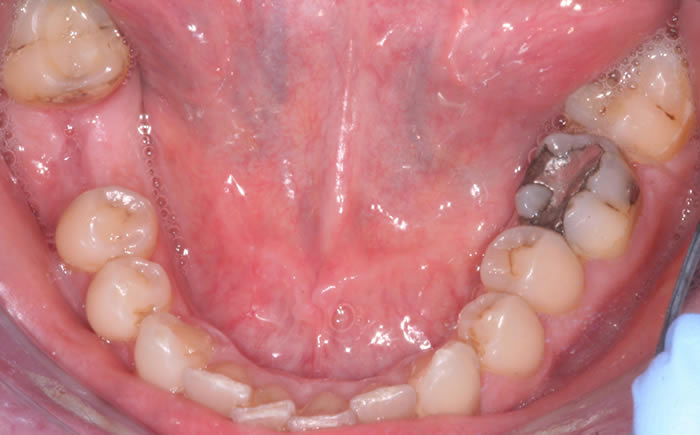

More back teeth replaced by dental implants

Case Three (2 images)

Case Four (4 images)

Case Five (4 images)

Case Six (8 images)

Case Seven (4 images)